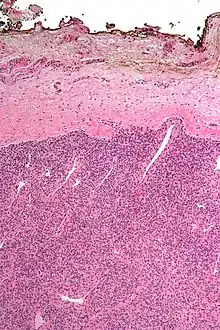

A resection margin or surgical margin is the margin of apparently non-tumorous tissue around a tumor that has been surgically removed, called "resected", in surgical oncology. The resection is an attempt to remove a cancer tumor so that no portion of the malignant growth extends past the edges or margin of the removed tumor and surrounding tissue. These are retained after the surgery and examined microscopically by a pathologist to see if the margin is indeed free from tumor cells (called "negative"). If cancerous cells are found at the edges (called "positive") the operation is much less likely to achieve the desired results.[1]: sections 1-2

Surgical margin in a surgery report defines the visible margin or free edge of "normal" tissue seen by the surgeon with the naked eye. Surgical margin as read in a pathology report defines the histological measurement of normal or unaffected tissue surrounding the visible tumor under a microscope on a glass mounted histology section.[4][5] A "narrow" surgical margin implies that the tumor exists very close to the surgical margin, and a "wide" surgical margin implies the tumor exists far from the cut edge or the surgical margin. Narrow surgical margin using the bread loafing technique suggests that residual cancer might be left due to false negative error. A surgeon often will perform a second surgery if a narrow surgical margin is noted on a pathology report.